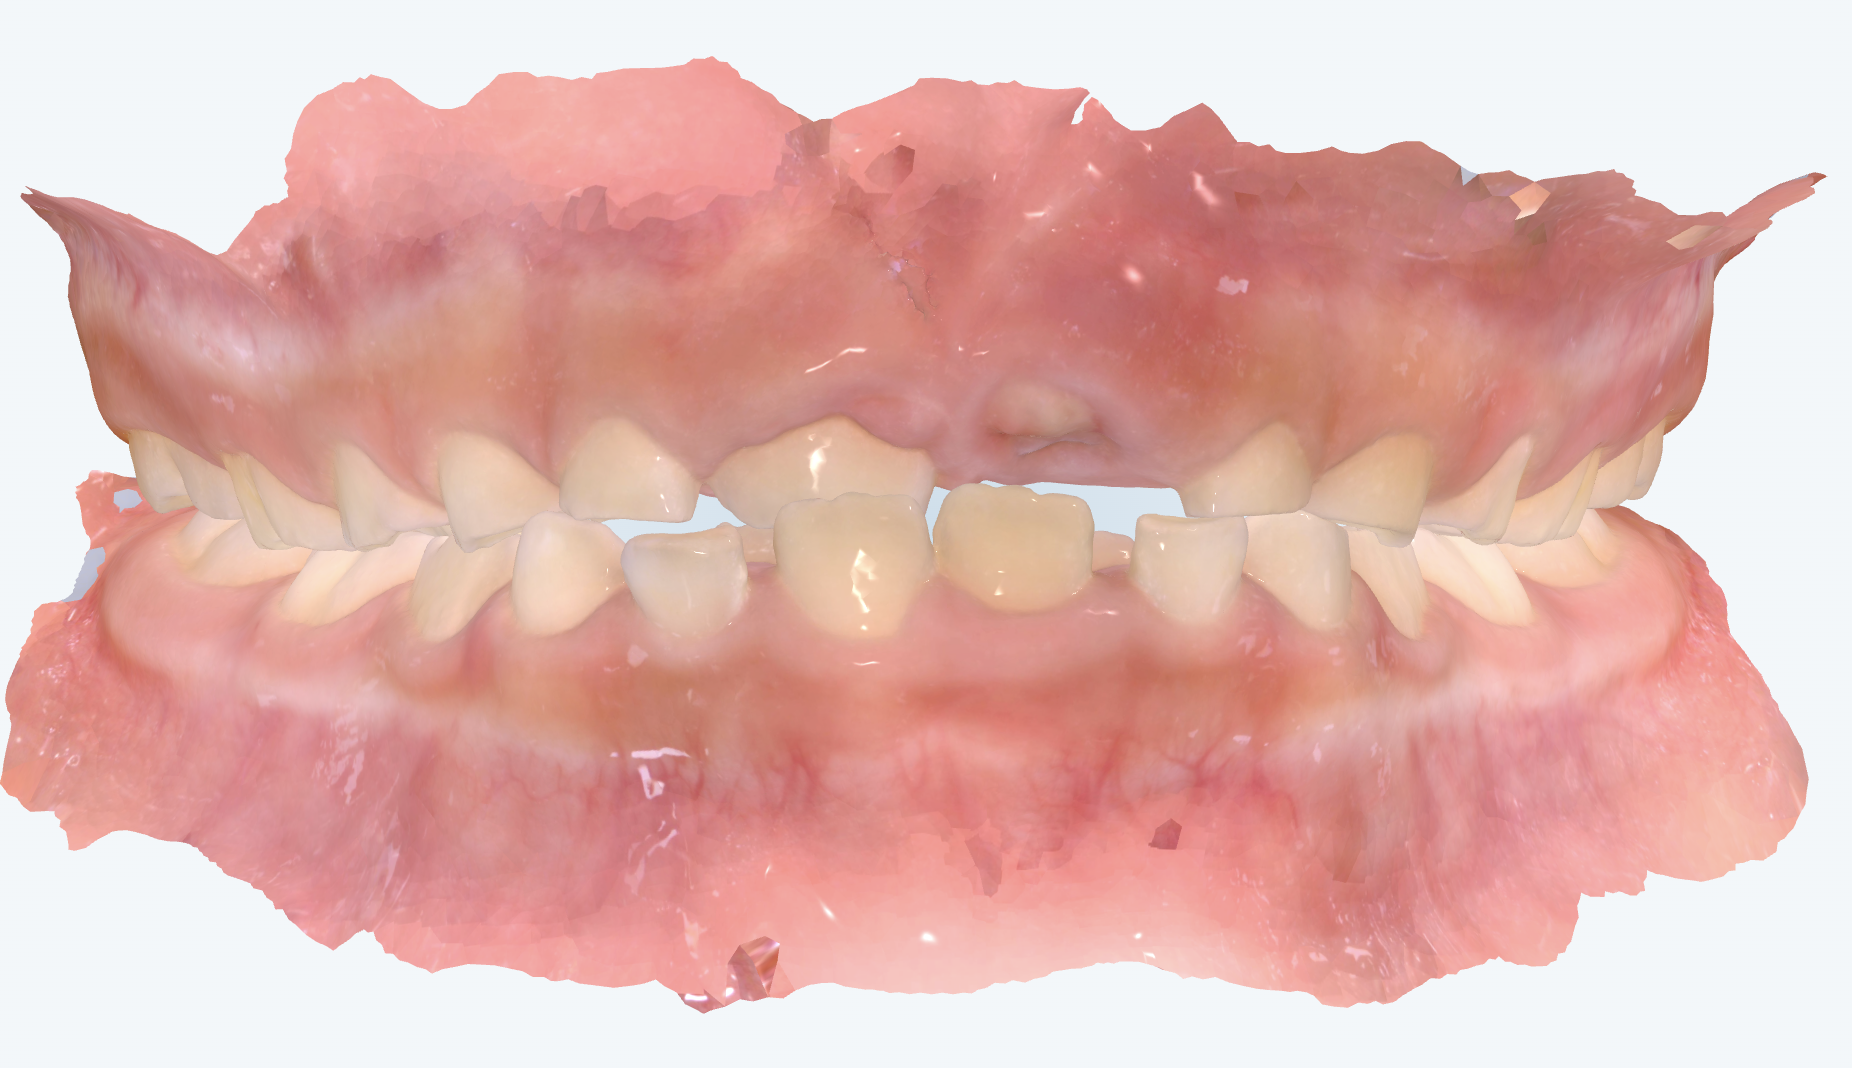

初診時の画像診断

永久歯の前歯が反対咬合になっていました。

下の前歯は乳歯の後ろから永久歯が生えてきて、2枚歯のようになっています。